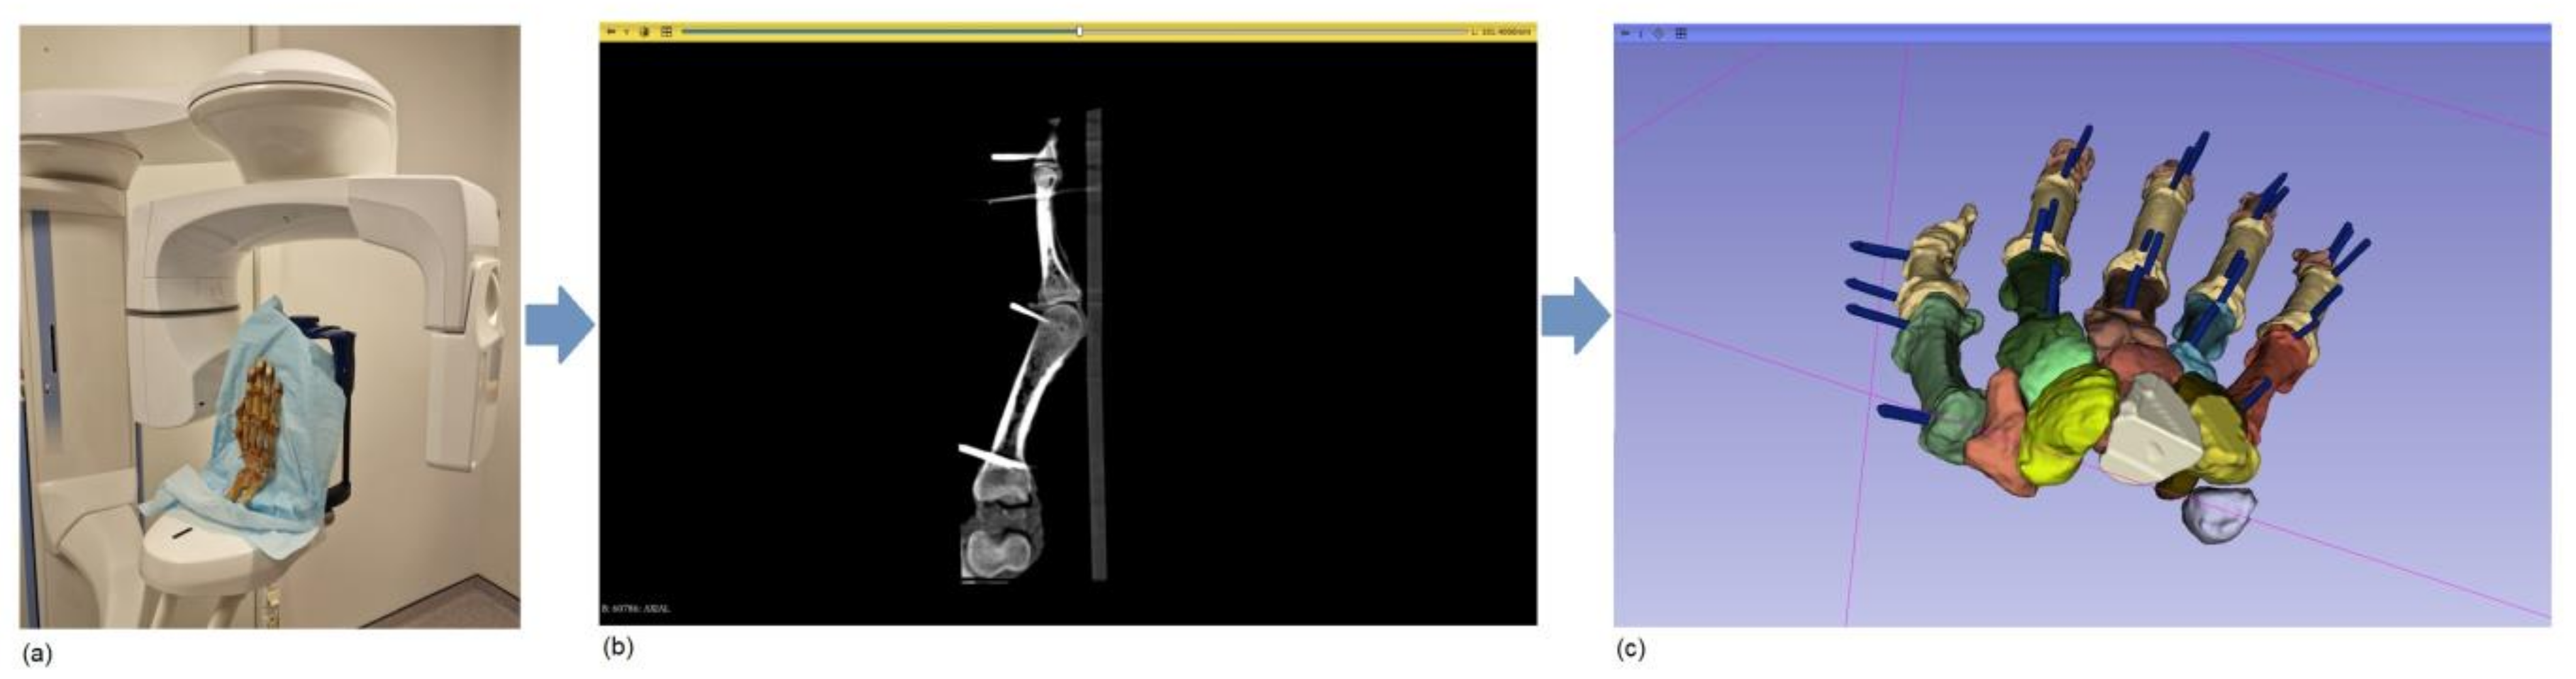

2.2. Image Acquisition

2.3. Image Processing